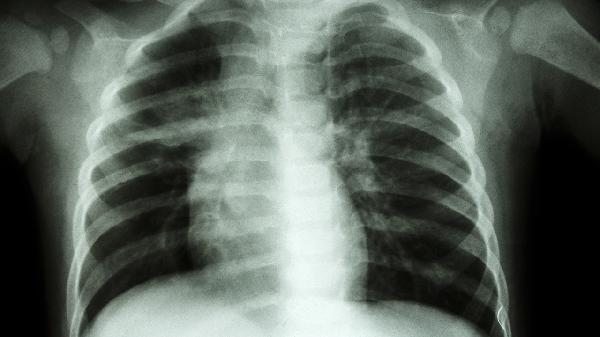

咳嗽发热伴随针刺样胸痛需就诊呼吸内科。肺炎、胸膜炎等呼吸系统疾病可能引发胸痛,CT检查可明确肺部病变。医生可能根据病原体类型使用阿莫西林克拉维酸钾片、盐酸左氧氟沙星胶囊等抗生素,合并胸腔积液时需穿刺引流。

外伤后局部胸痛或气胸复发建议胸外科评估。肋骨骨折、自发性气胸等需影像学检查,少量气胸可观察,大量气胸需闭式引流术。胸外科还处理纵隔肿瘤等需手术的胸部疾病。